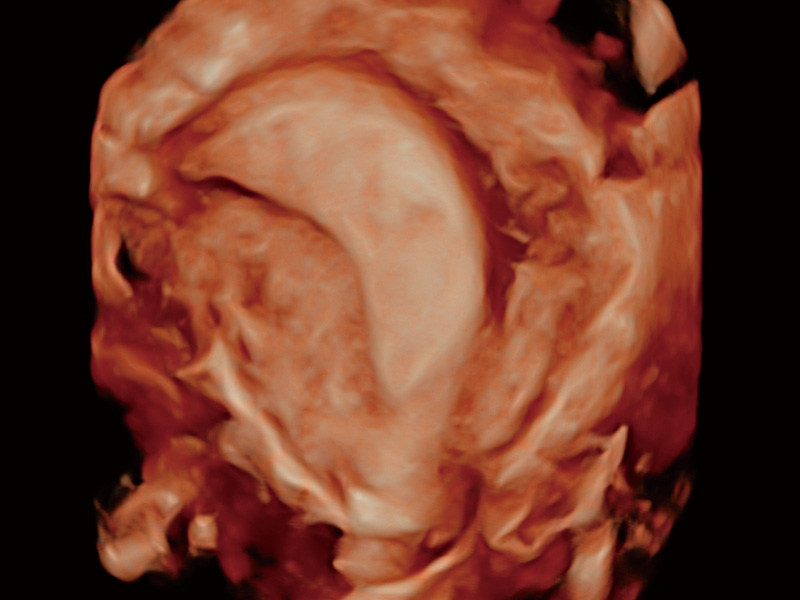

“生育问题”即关系民族复兴,也关系亿万家庭的幸福。随着婚育年龄推迟、社会压力增加等因素,越来越多人群也面临着“生不出、生不好”的问题。辅助生殖作为治疗不孕不育最有效的方法之一,也逐渐成为育儿新希望。而超声检查能为生殖需求人群的初诊评估提供宝贵的信息。 P20 Elite是狗万官方网站匠心打造的一款生殖应用型彩超。她继承狗万官方网站高端极光平台,突破性地将多款新型芯片及硬件模块进行整合,均衡了高端系统性能与小巧灵动机身。P20 Elite卓越的图像质量搭载专科探头,旨在为您提供全面的辅助生殖解决方案。

P20 Elite配备了丰富的生殖探头群和临床应用功能,在卵泡监测、穿刺取卵、胚胎移植、妊娠确认等领域,为生殖需求人群提供了新的临床机会,重新定义高端超声如何应用于生殖健康检查。